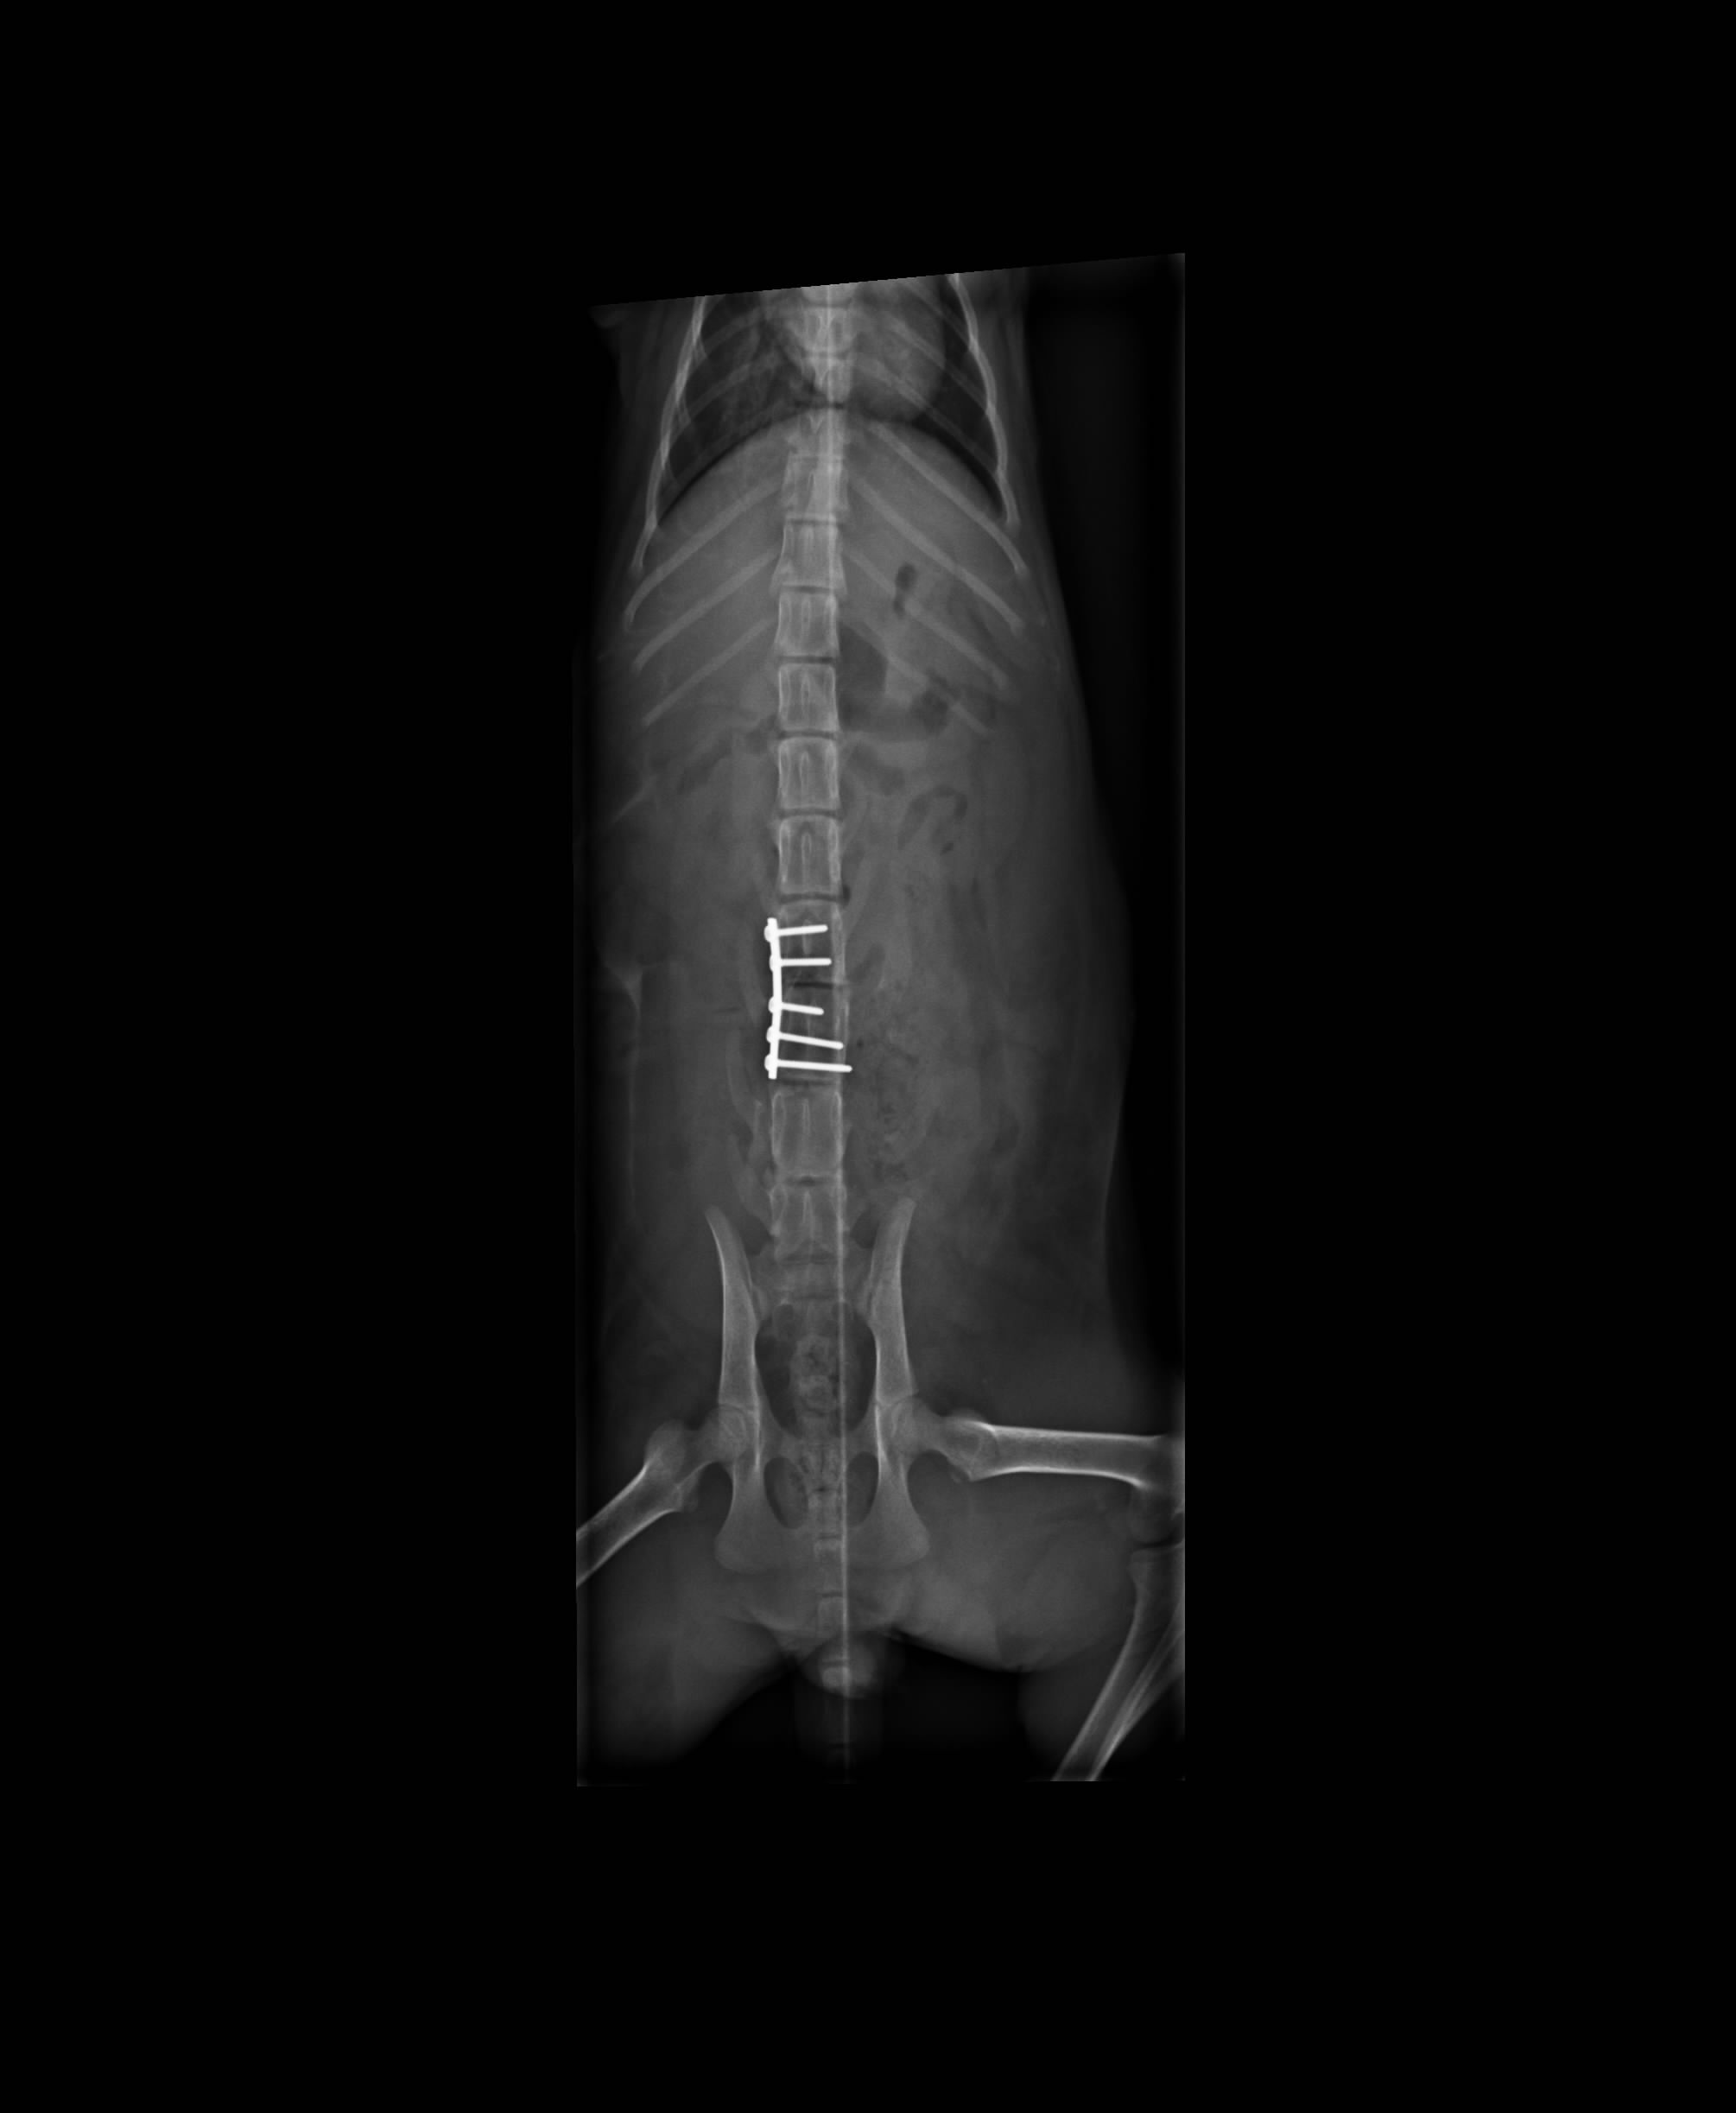

把發發送進醫院之後,經過醫生細心檢查後,醫生說,小喵還在發育階段,骨骼當中含有生長板,生長板因為要讓骨骼長大,存有不成熟的細胞所以非常脆弱。小喵的脊椎斷裂(被側面撞擊到),日後癱瘓的機率很高,且要須仰賴人工協助,也無法自行排便排尿。

2.X光400*2+400*2=1600

5.脊椎固定手術25000

Tota 38400*0.7+250=27130